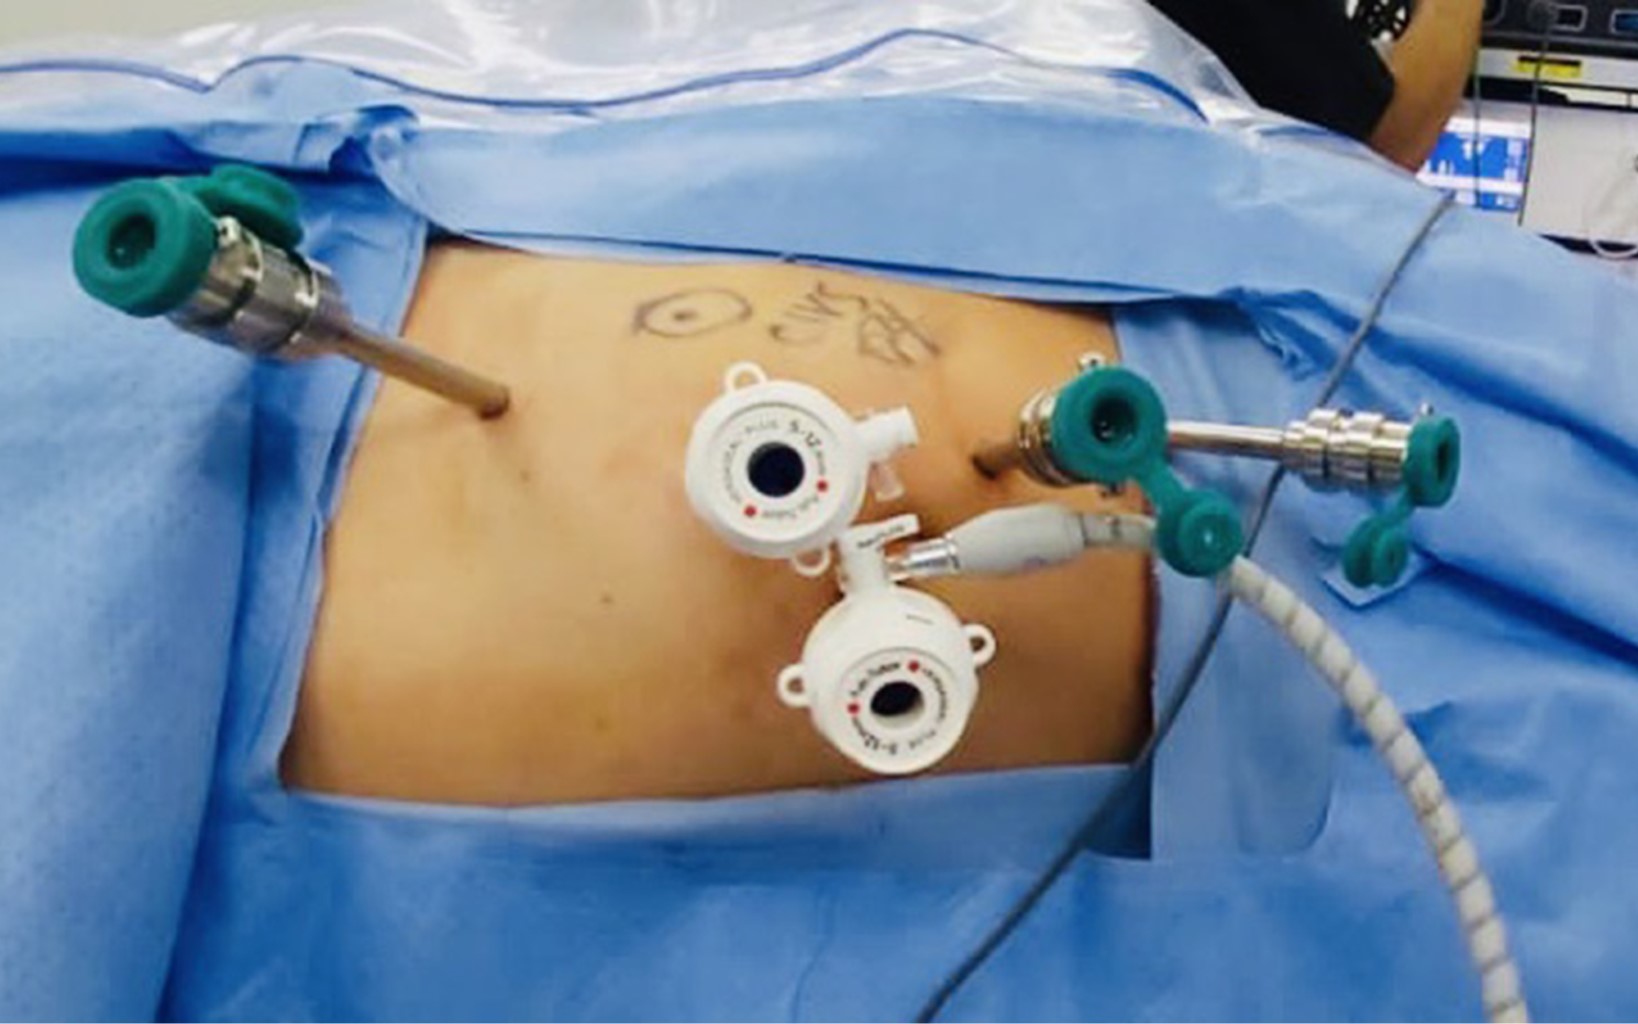

Técnica quirúrgica

Bajo anestesia general balanceada, se colocó al paciente en decúbito lateral derecho con ligera flexión de la mesa para maximizar el espacio de trabajo. Se colocó un primer trocar de 12 mm con técnica de Hasson, con una adecuada insuflación; después, se colocaron tres trocares robóticos de 8 mm y un trocar de 12 mm para asistente bajo visión directa, como se muestra en la Figura 1. Se acoplaron los brazos del robot a los trocares y se realizó exploración de la cavidad abdominal sin encontrar adherencias.